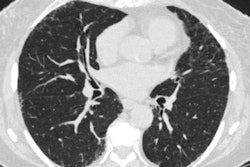

A personalized lung cancer screening model used with patients with pulmonary nodules identified on low-dose CT (LDCT) helps clinicians determine how to follow up better than rule-based protocols, researchers have found.

Up to half of screened individuals have at least one pulmonary nodule on lung cancer screening, and determining the optimal time for follow-up testing of these nodules can be a challenge, the authors explained.

To address the problem, the group developed and validated a modeling schema for predicting lung cancer using data from 1,809 patients in the National Lung Screening Trial (NLST) between the ages of 55 and 74 with pulmonary nodules. Of these cases, 1,206 were used for the development of the schema and 603 for its validation. The model included predictors such as age, obesity, family history of lung cancer, smoking pack-years, and nodule information; the researchers assessed patients' cancer risk profiles at baseline and at two follow-up screening rounds, one at three months after initial screening and another at 12 months.